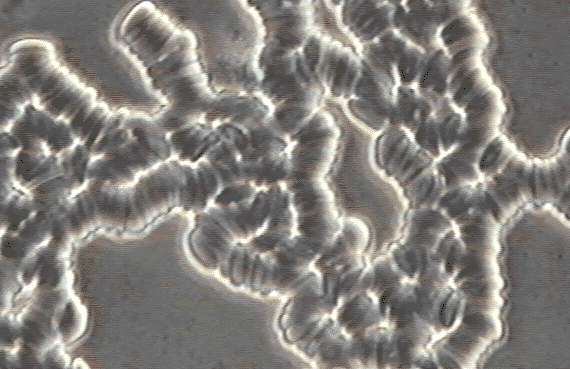

Do your red blood cells look like this? Mine did!

-W.S. 1/22/98

Before Microhydrin

Before

Microhydrin™

(See enlargement-96k)

Rouleau (clumped red blood cells) severely limits the access and availability of required nutrients and oxygen. An antioxidant may improve this.

Only 15 minutes after taking Microhydrin™ my cells looked like this!

After Microhydrin

After

(See enlargement-80k)

With Microhydrin,™ normal separation and fullness of the red blood cells returns aiding nutrient and oxygen absorption.